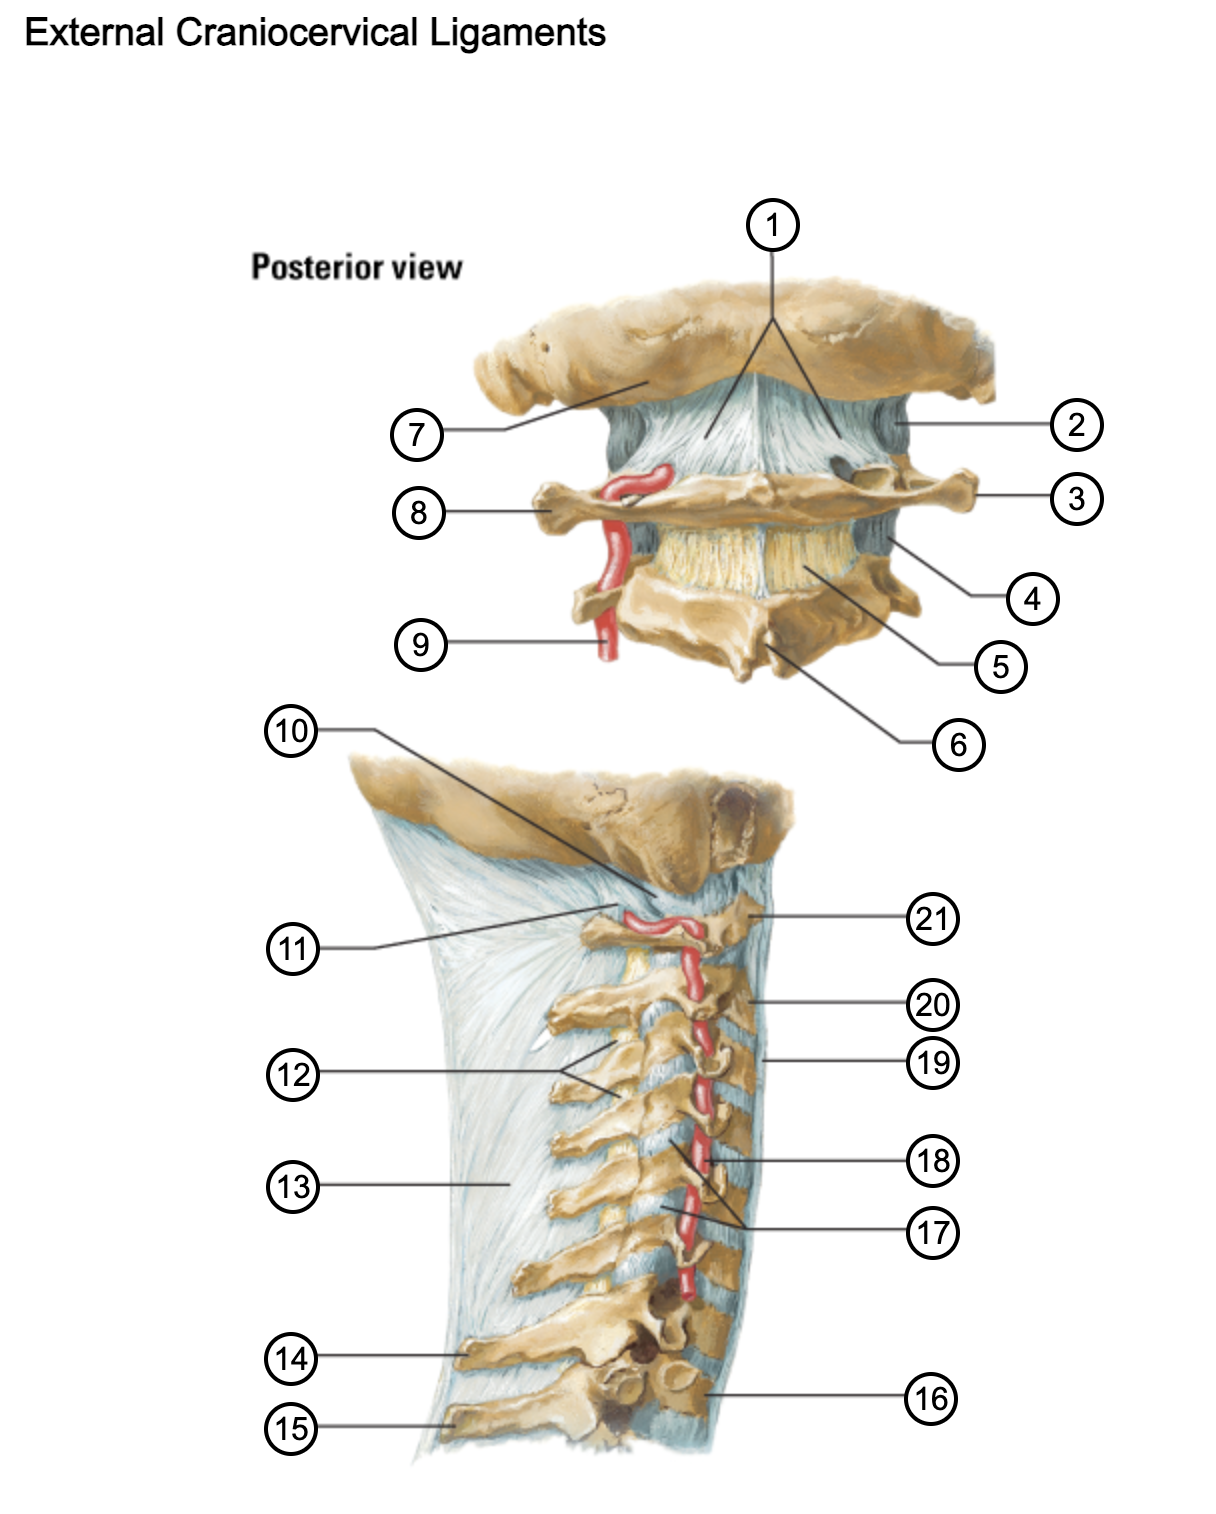

1

posterior antlantooccipital membrane

2

capsule of atlantooccipital joint

3

transverse process of atlas (C1)

4

capsule of lateral atlantoaxial joint

5

ligamenta flava

6

spinous process

7

occipital bone

8

transverse process of atlas (C1)

9

vertebral artery

10

capsule of atlantooccipital membrane

11

posterior atlantooccipital membrane

12

ligamenta flava

13

nuchal ligament

14

spinous process of C7 vertebra

15

spinous process of T1 vertebra

16

T1 vertebra

17

zygapophysical joints (C4-5 and C5-6)

18

vertebral artery

19

anterior longitudinal ligament

20

body of axis

21

Atlas (C1)